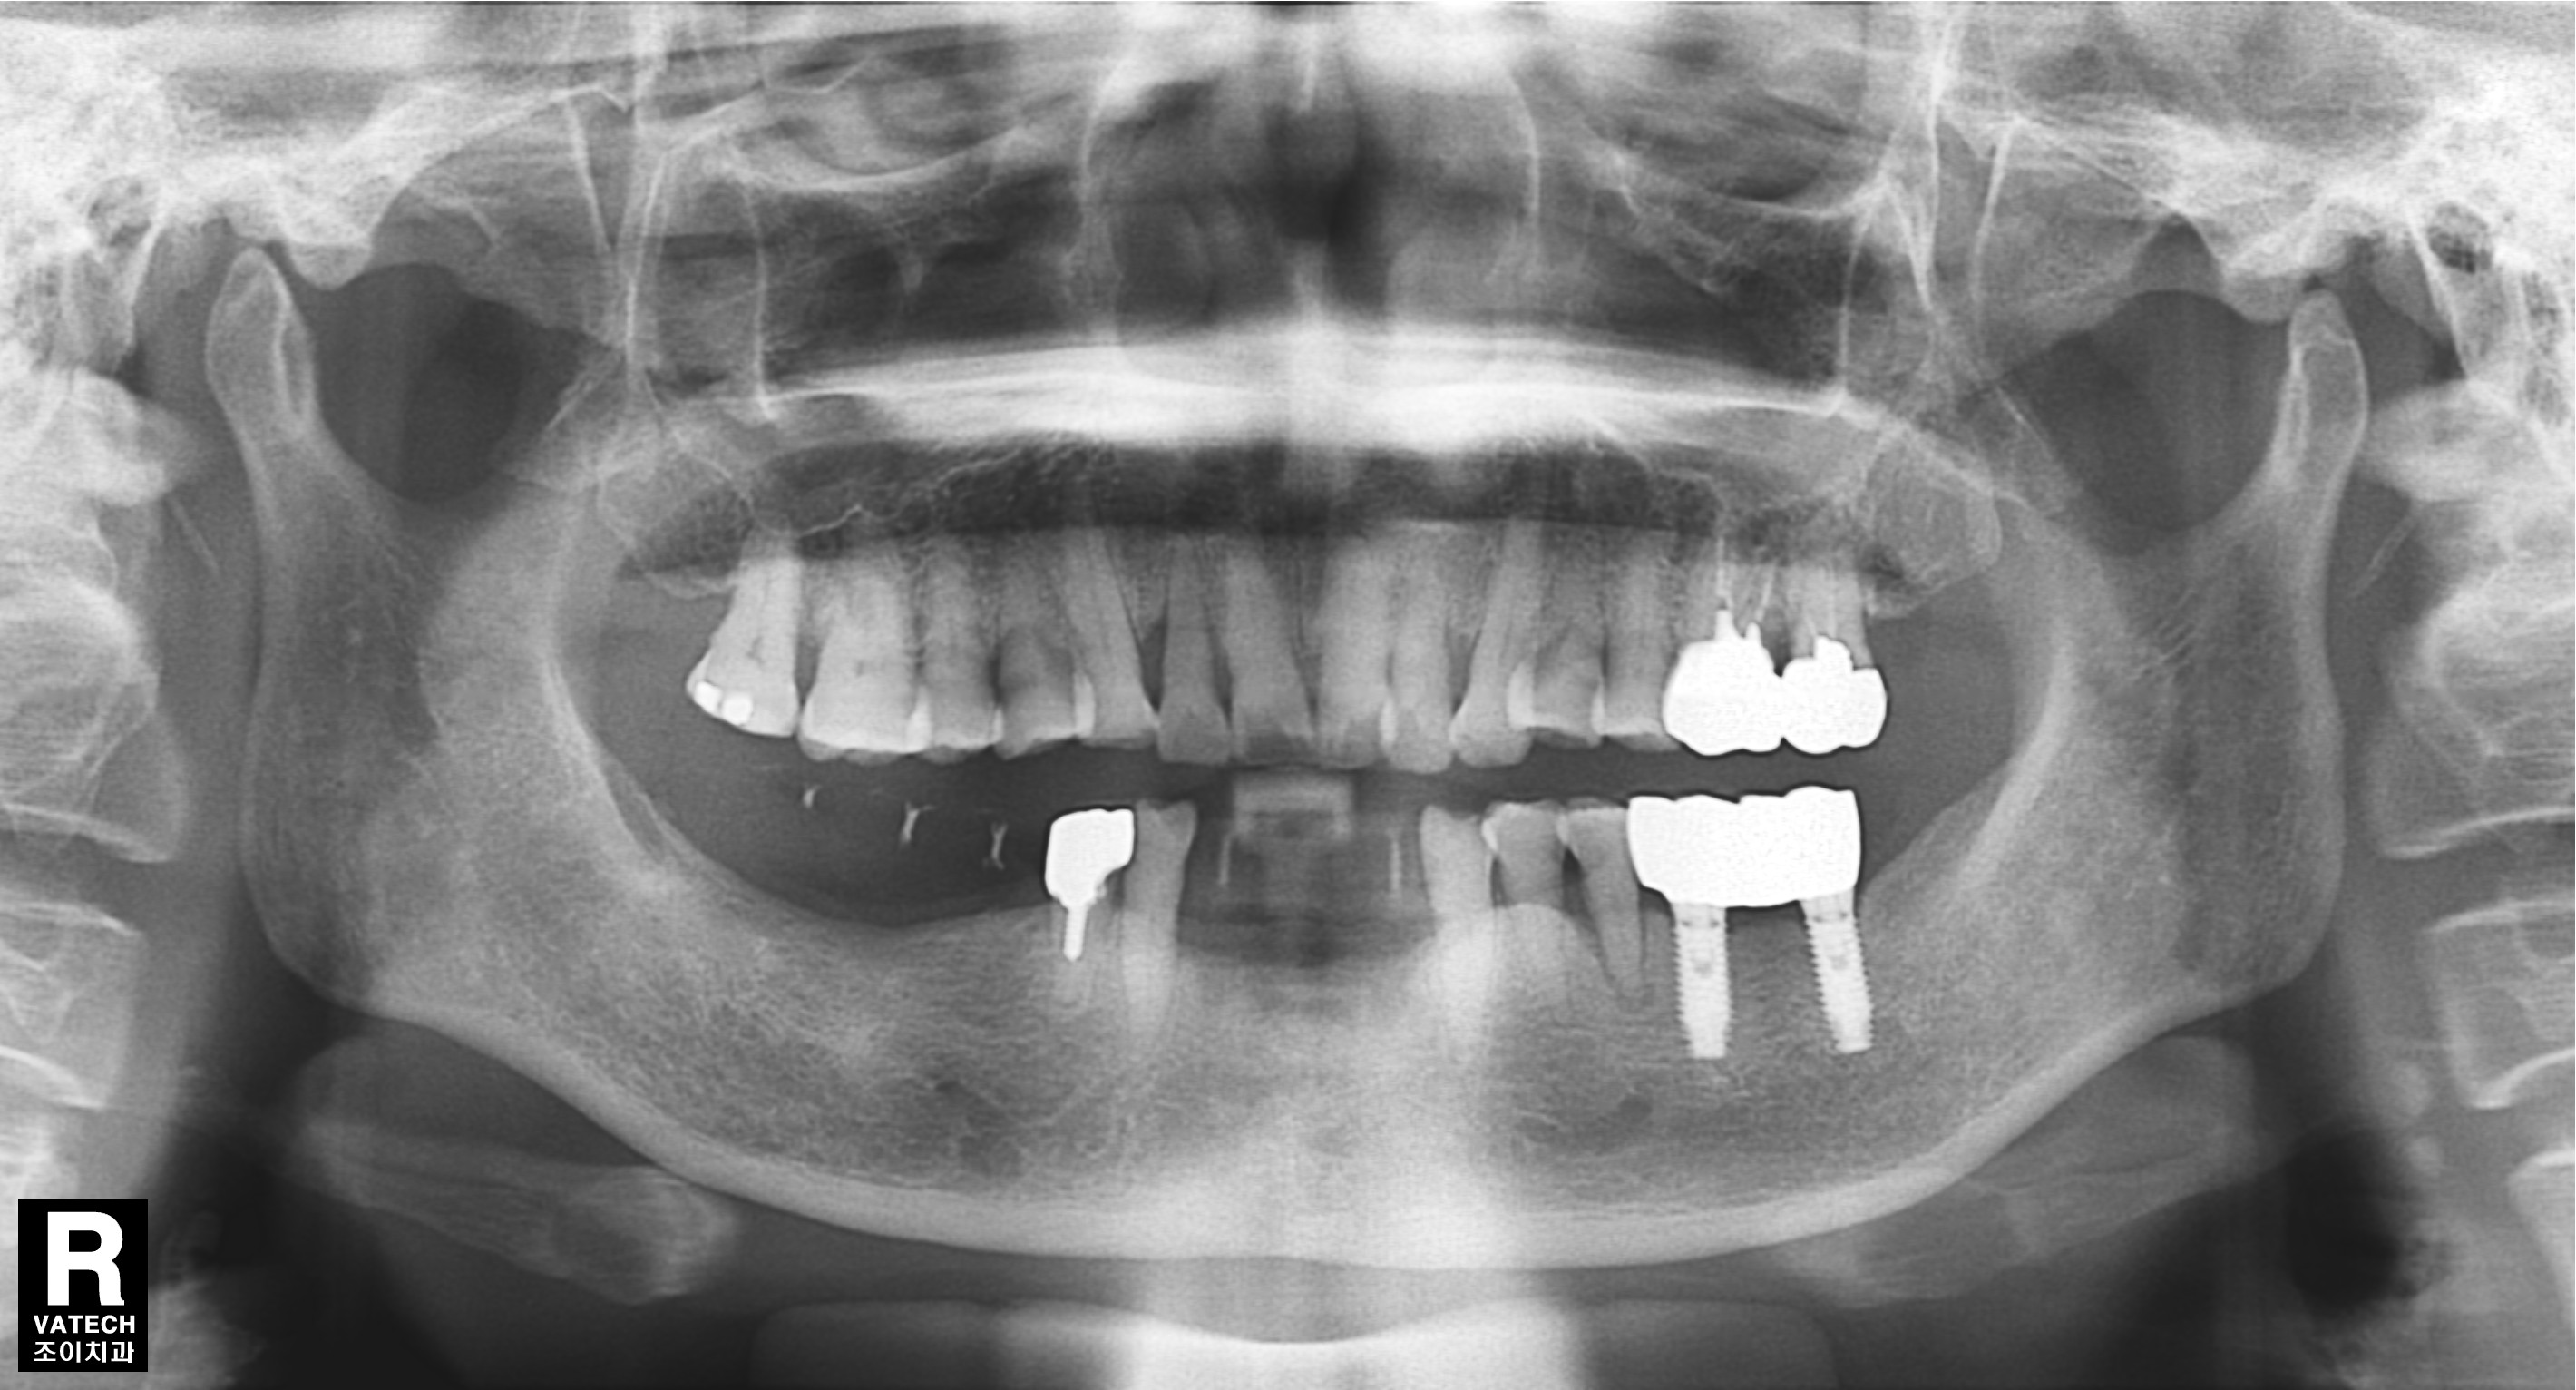

임플란트 보철. 조이치과에서는 임플란트 시술 후 관리를 위하여 보철물 위에 스크류홀을 형성하는 SCRP보철을 주로 이용합니다.

SCRP를 만들기 위해서는 정확한 임플란트가 정확한 위치와 경사로 심겨져야합니다.